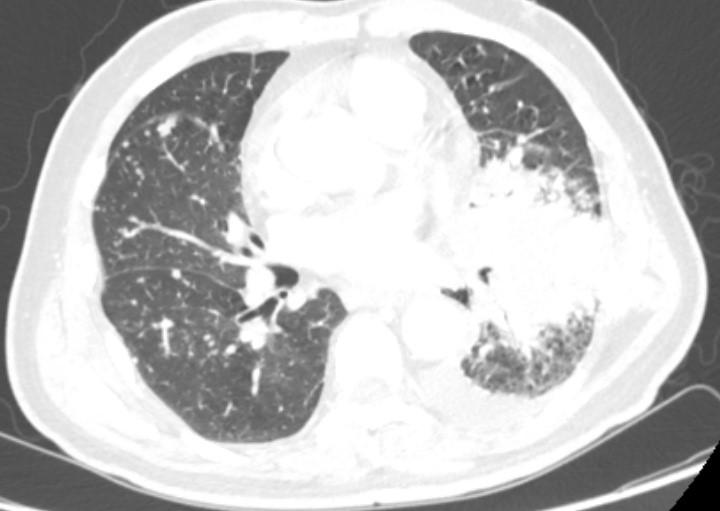

小细胞肺癌(SCLC)是一种高度侵袭性的恶性肿瘤 ,约占肺癌总数的14%。由于其发病机制复杂、驱动基因不明确,SCLC的治疗进展缓慢, 患者的中位总生存期仅为8-11个月,5年生存率不足5% 。面对这一严峻形势, 免疫治疗为SCLC的治疗带来了新的希望。